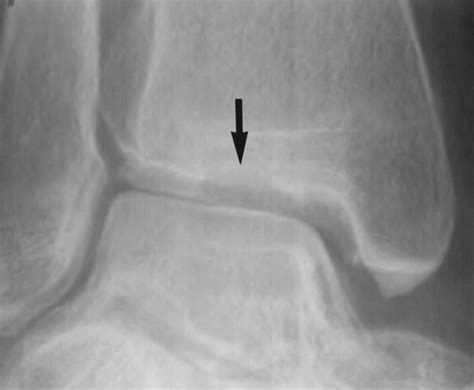

• Imaging Tests: Imaging tests, such as X-rays, MRI, or CT scans, are used to visualize the bone and cartilage within the ankle joint. These tests can help identify the location and extent of the lesion.

Imaging tests are particularly important in diagnosing Osteochondritis Dissecans Ankle, as they can provide detailed information about the condition of the bone and cartilage.